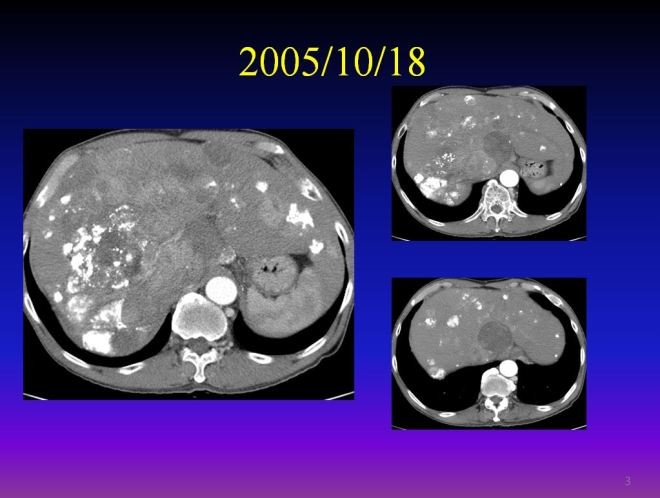

다음은 색전술 1년 뒤인 2005년도 CT 사진이다.

간에 있던 암들이 현저히 소실이 되어서 암이 보이는 부분만 수록하였으므로 위와 level이 조금 다르다. 하지만 이전에 보이던 간 좌엽의 우들두들하던 경계면의 간이 약간 재생되어서 자라면서 매끈해졌고 리피오돌 uptake 된 부분이 현저히 줄어들었다. 다음은 2004년과 약 8개월 뒤인 2005년도의 비교 사진이다. 우리는 두 사진을 비교해 볼 때 색전술이 매우 잘 반응을 했음을 알 수 있다.